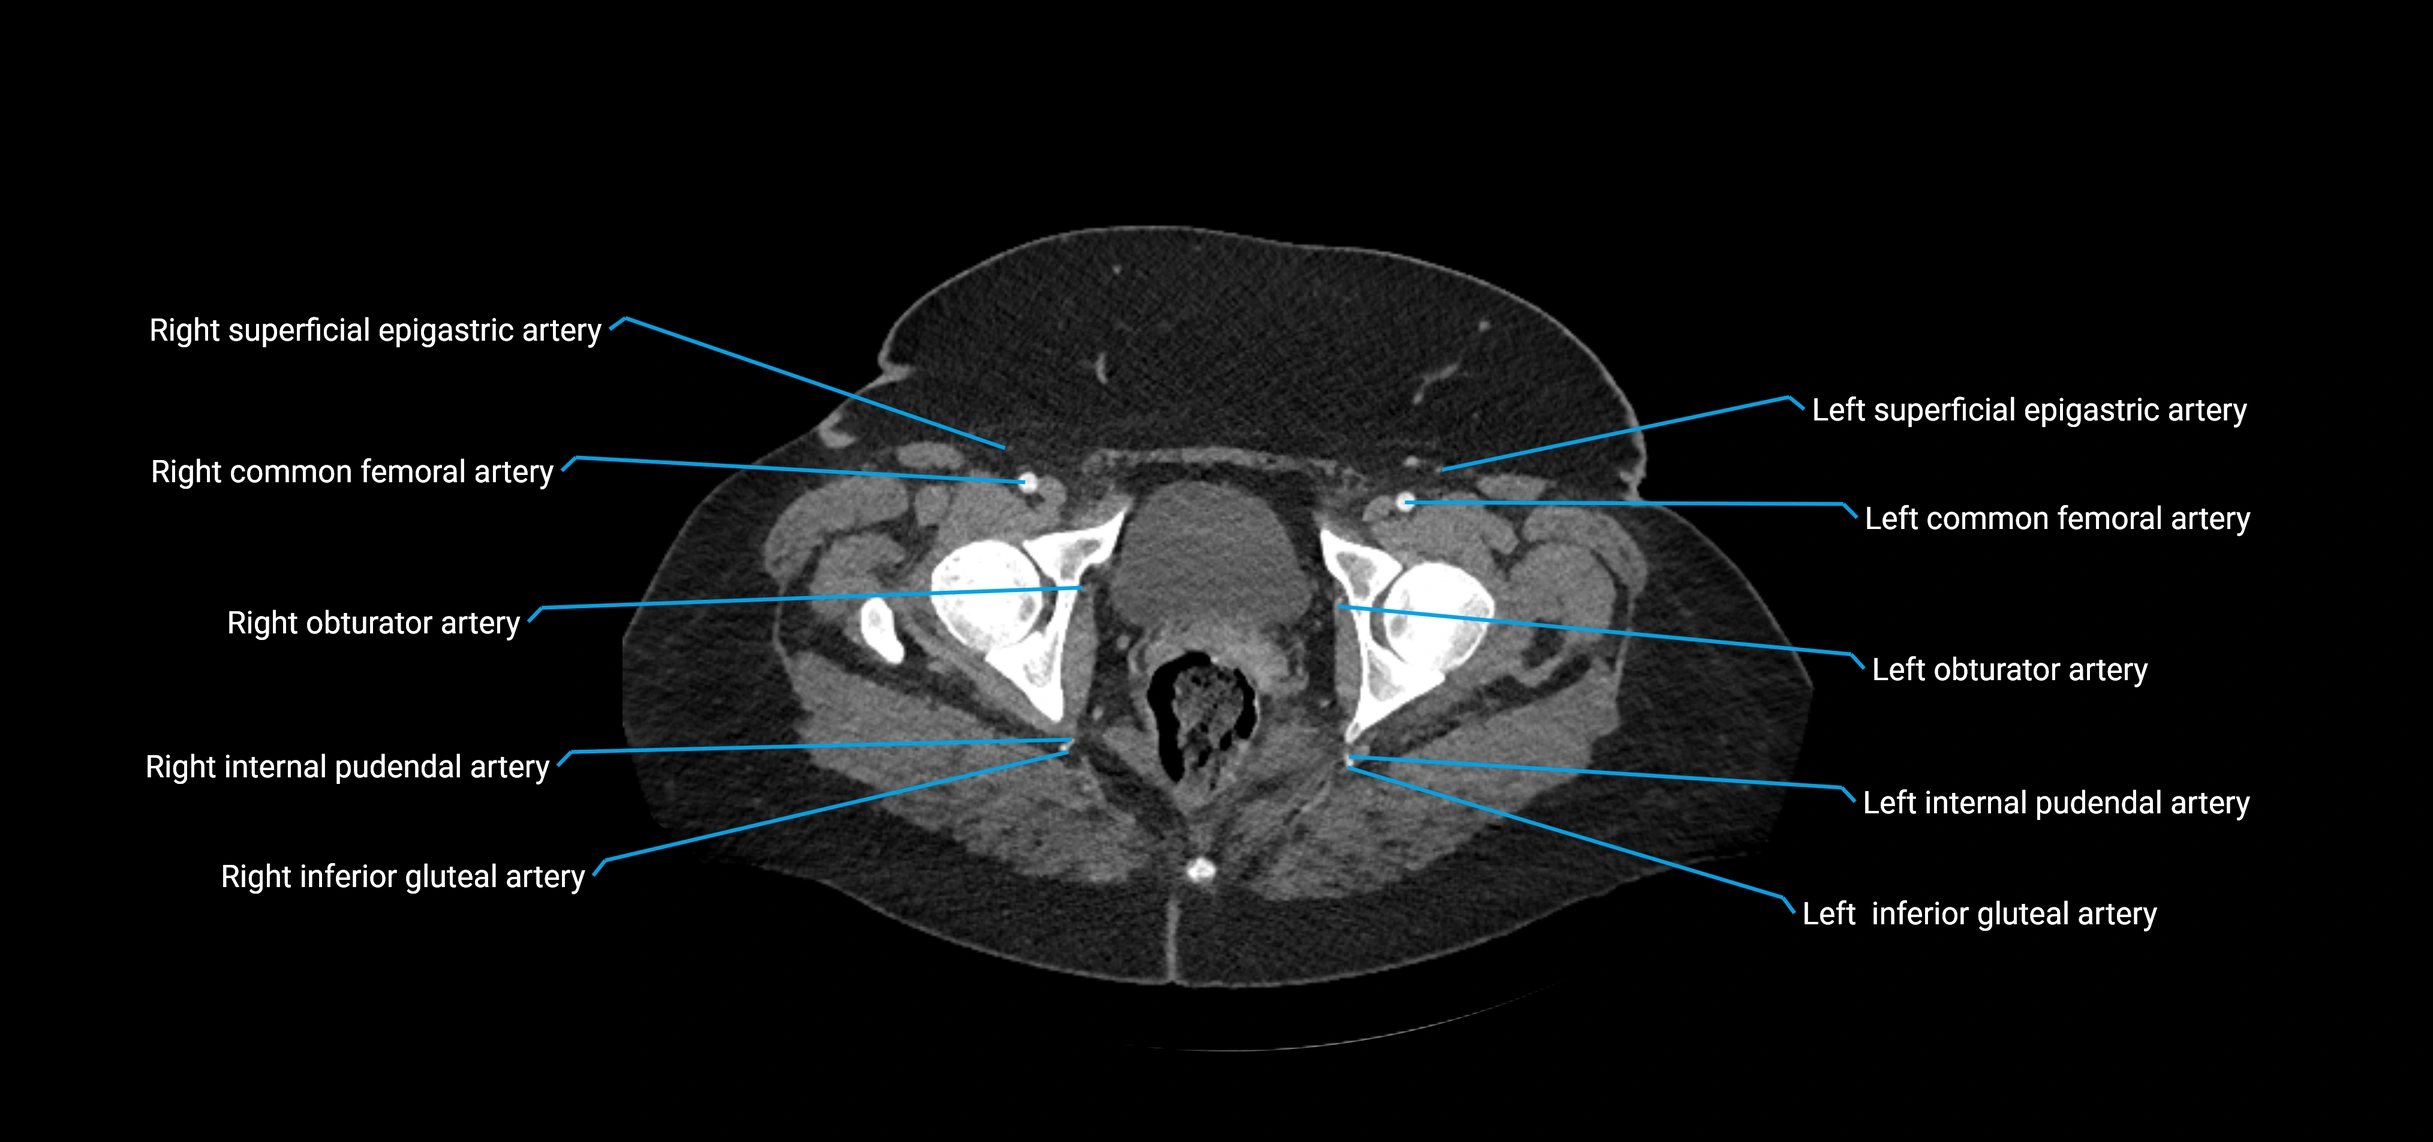

Contrast-enhanced CT (CTA):

• Gold standard for abdominal aortic imaging

• Provides excellent detail of lumen, wall, aneurysm, thrombus, and branch vessels

• Multiplanar and 3D reconstructions help in aneurysm measurement, stent graft planning, and dissection evaluation